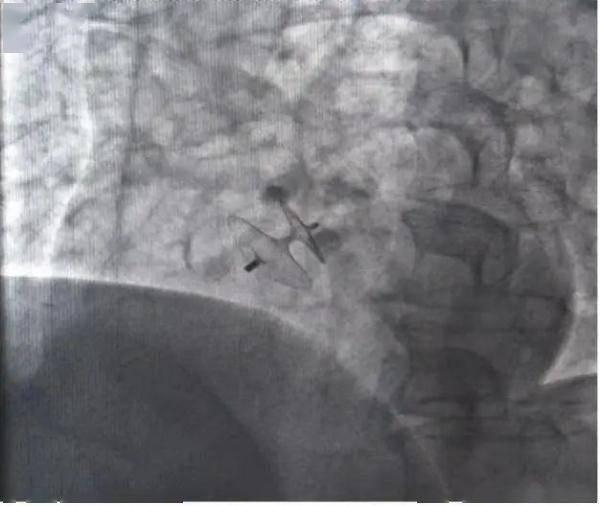

封堵器

介入封堵

邵中兴介绍,为了“堵”上心脏上的这一“小洞”,医生通常将从患者的右侧股静脉即大腿根部置入微导管,从而建立通道。“形象地说,卵圆孔的封堵器像个伞面。收起时,封堵器呈长条形通过微导管送入心脏,释放后,它可以像撑开伞那样膨胀起来,在左心释放左盘,再拉到右心释放右盘,相当于夹了起来。”